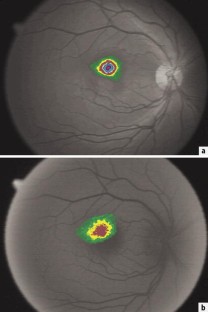

Abb. 1a,b.

An 18 gesunden Probanden (mittleres Alter: 23,9 Jahre) wurde die örtliche Verteilung der optischen Dichte proportionalen Xanthophyllkonzentration aus monochromatischen Fundusfotografien im blauen Spektralbereich sowie aus Autofluoreszenzaufnahmen bestimmt. Die Aussagefähigkeit der Parameter Gesamtkonzentration, maximale und mittlere Konzentration wurden verglichen.

Im Mittel über alle Probanden wurde in guter Übereinstimmung mit der Literatur eine maximale optische Dichte des Makulapigmentes von 0,29±0,08 aus den Reflexionsaufnahmen bestimmt. Zur Einschätzung des globalen Xanthophyll-Status eines Patienten scheint jedoch die mit der Maximalkonzentration korrelierende Gesamtkonzentration geeigneter zu sein. Die geringe Intensität der Autofluoreszenzaufnahmen lässt diese als zur Bestimmung der Xanthophyllkonzentration weniger geeignet erscheinen.

The local distribution of xanthophyll density was determined from monochromatic blue reflection images and autofluorescence images of the fundus in 18 healthy volunteers (mean age: 23.9 years). The significance of the parameters maximal, global, and mean concentration were compared.

The maximal optical density of xanthophyll determined from reflection images was found to be 0.29±0.08 (mean for all test persons) which is in good agreement with literature data. The total xanthophyll concentration which is proportional to the maximal density, appeared to be appropriate to describe a person's overall xanthophyll status. Because of the low intensity of autofluorescence images, these are less useful for the determination of the xanthophyll concentration.